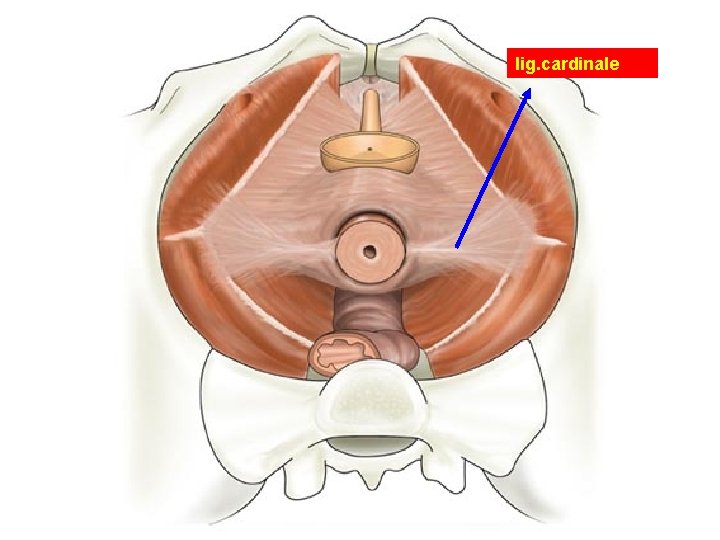

lig. cardinale

Ligaments of the Uterus • Lig. Sacrouterinum (LUNA) • Lig. Latum Uteri • Lig. Rotundum – Cyst of Nuck canal – A. Sampson – Lig. Cardinale most important lig.